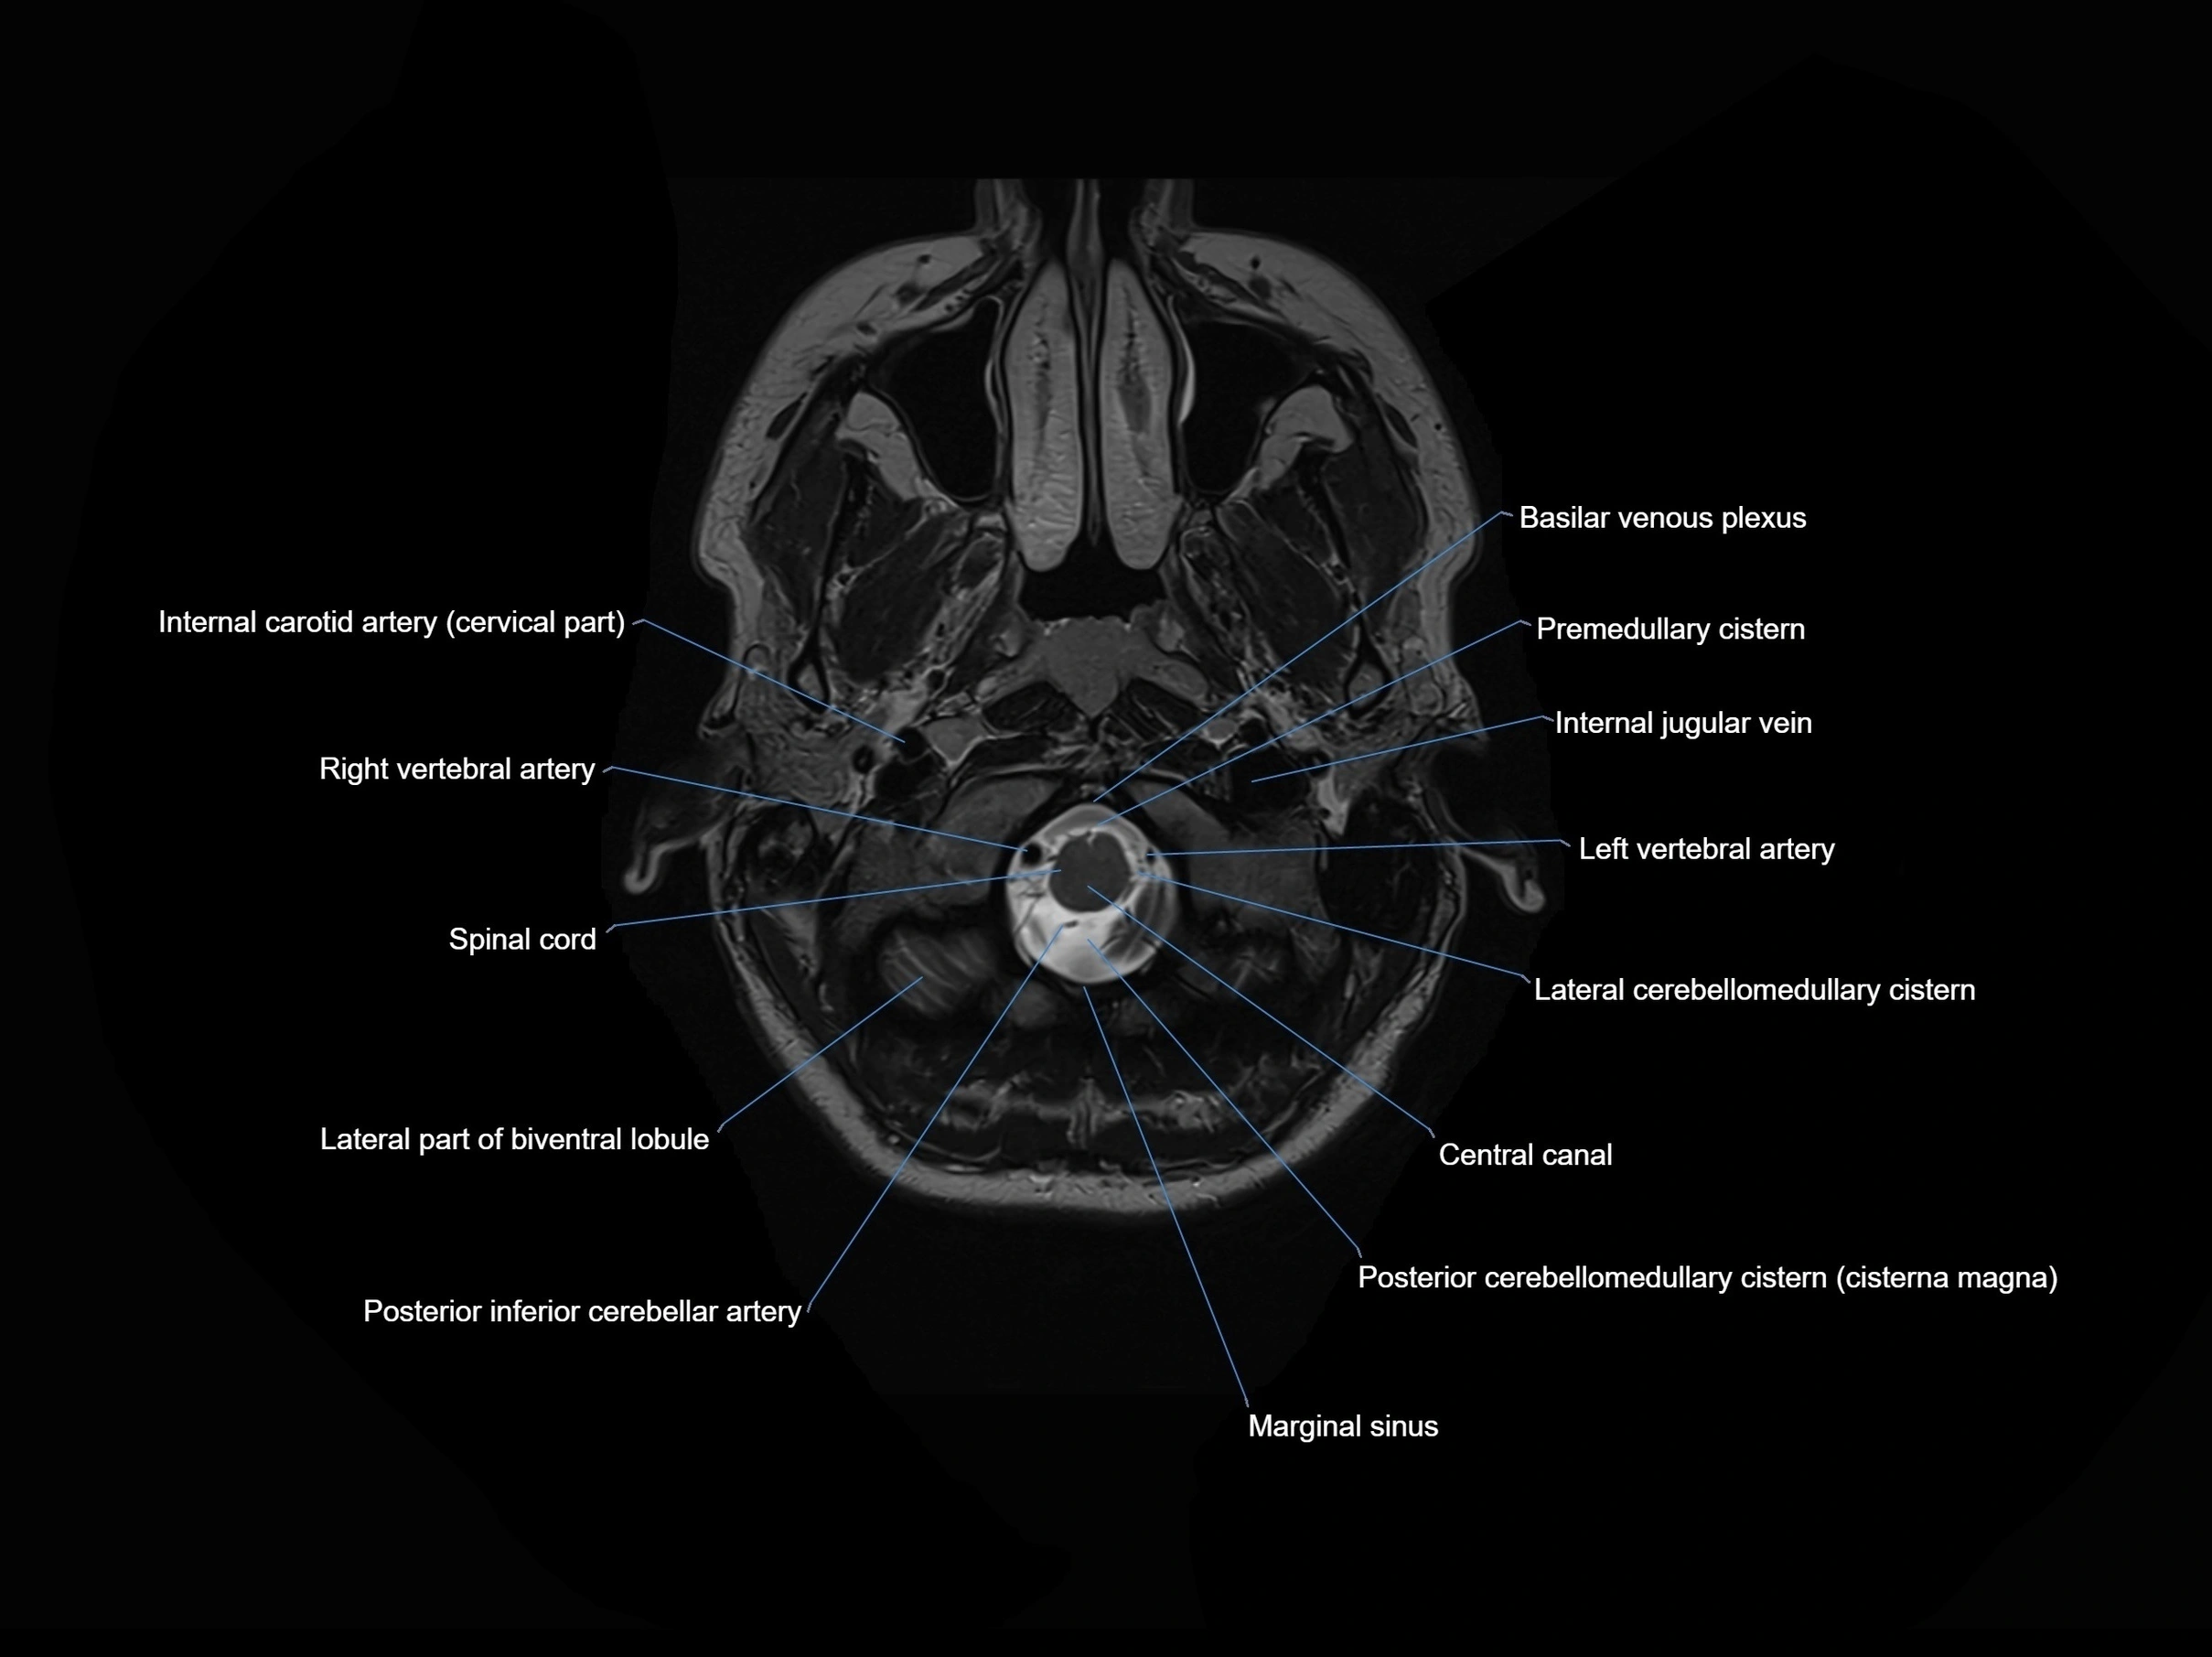

- Central canal

- Internal carotid artery (cervical part)

- Internal jugular vein

- Lateral cerebellomedullary cistern

- Left vertebral artery

- Marginal sinus

- Posterior cerebellomedullary cistern (cisterna magna)

- Posterior inferior cerebellar artery

- Premedullary cistern

- Right vertebral artery

- Spinal cord

- Basilar venous plexus